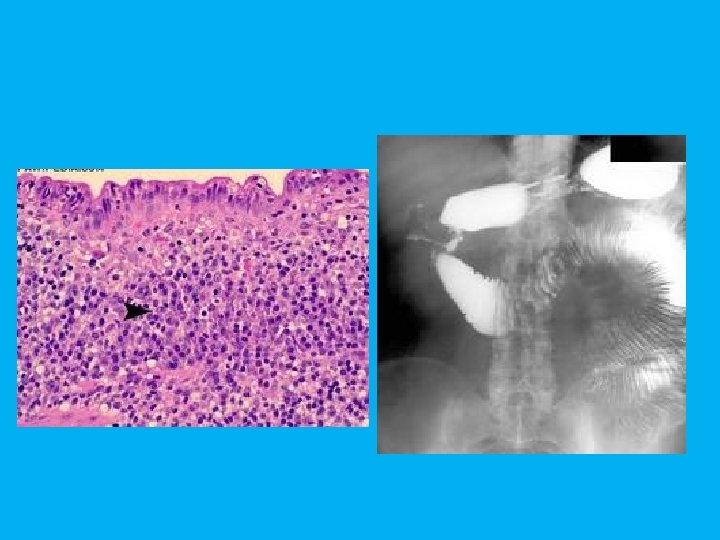

Case 26 • A middle age man presented with crampy abdominal pain and melena. There is history of kidney transplant and use of cyclosporine and azathioprine for 6 years. • You see the small bowel transit and the histology of resected segment.

• What do you see in the radiograph? • Bowel obstruction in jejunum • Bowel obstruction in duodenum • Gastric outlet obstruction • What is the most probable diagnosis? • Lymphoma • CMV infection • Tuberculosis